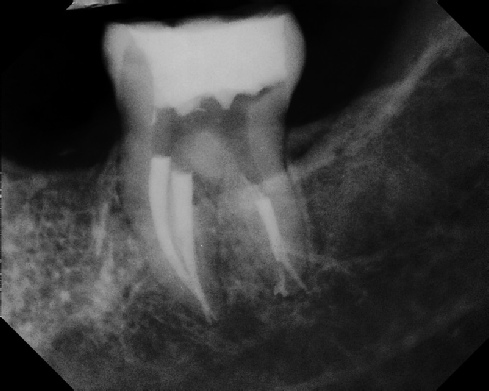

COMPLICATED ANATOMY LARGE LESIONS CALCIFIED CANALS PERFORATION / RESORPTION SEPARATED INSTRUMENTS SURGICAL CASES RETREATMENT / pOST REMOVAL OPEN APICES ACCESS THRU CROWNS Root Canal Case Portfolio

Pre-op Post-op 1 Post-op 2